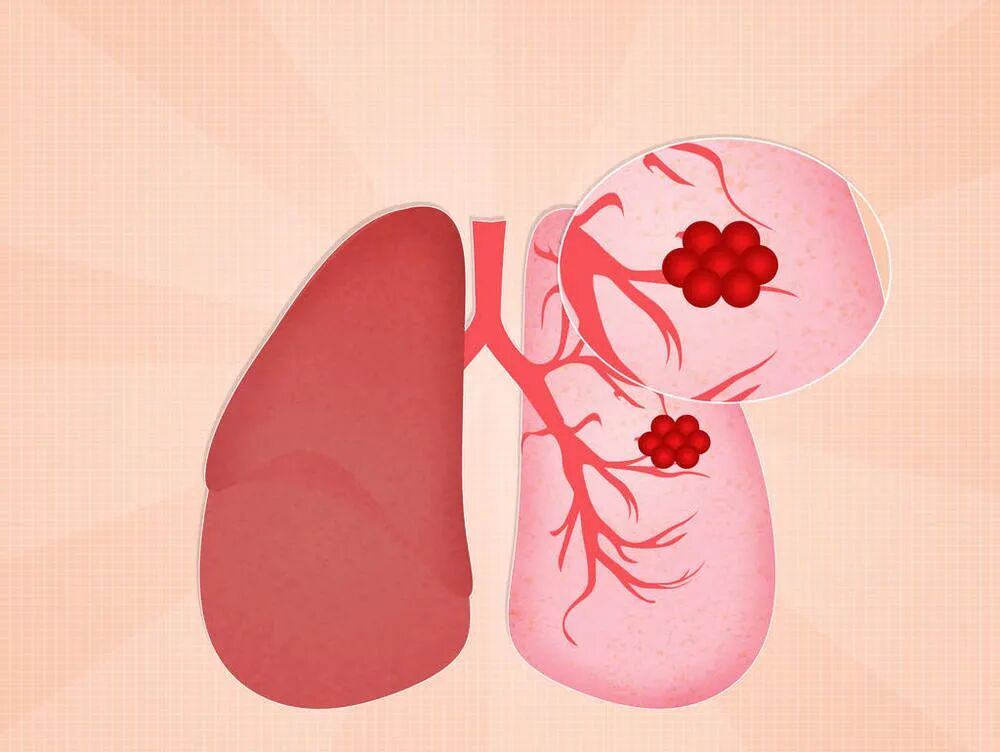

磨玻璃结节,也是我们常说的GGO(Ground GlassOpacity),指在高分辨CT中包含有支气管和血管成分的密度增高影。因其在CT上表现为云雾一样的淡薄影,看起来像是磨砂玻璃,从而得名。

磨玻璃结节会是肺癌吗?

磨玻璃结节是包含有良性、恶性一大类疾病的共同影像学表现。可以是一过性的表现,也可以持续性存在。

磨玻璃结节GGO(Ground Glass Opacity)可以是炎症、局部的出血、水肿、纤维增生,也可能是不典型腺瘤样增生(AAH),当然也可能是我们所害怕的肺癌。